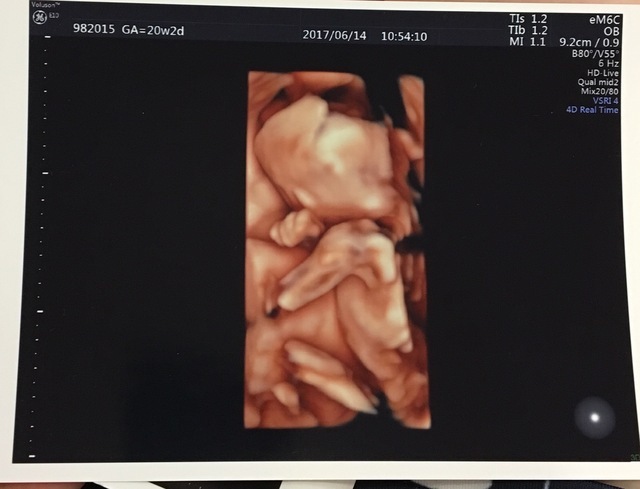

20週2日(20w2d・女の子)|まいのん さん(33歳)

エコー写真撮影時のエピソード:

初めての4Dできれいに撮れました♡ やっぱり、動いてるのをみるとかわいさが増え、愛おしさも倍増!!

横顔だけ見ても鼻筋スーッととーってて美人!といわれて調子にのっています╰(*´︶`*)╯♡ でもまだ半分なのでこれからどうかわるか楽しみです!